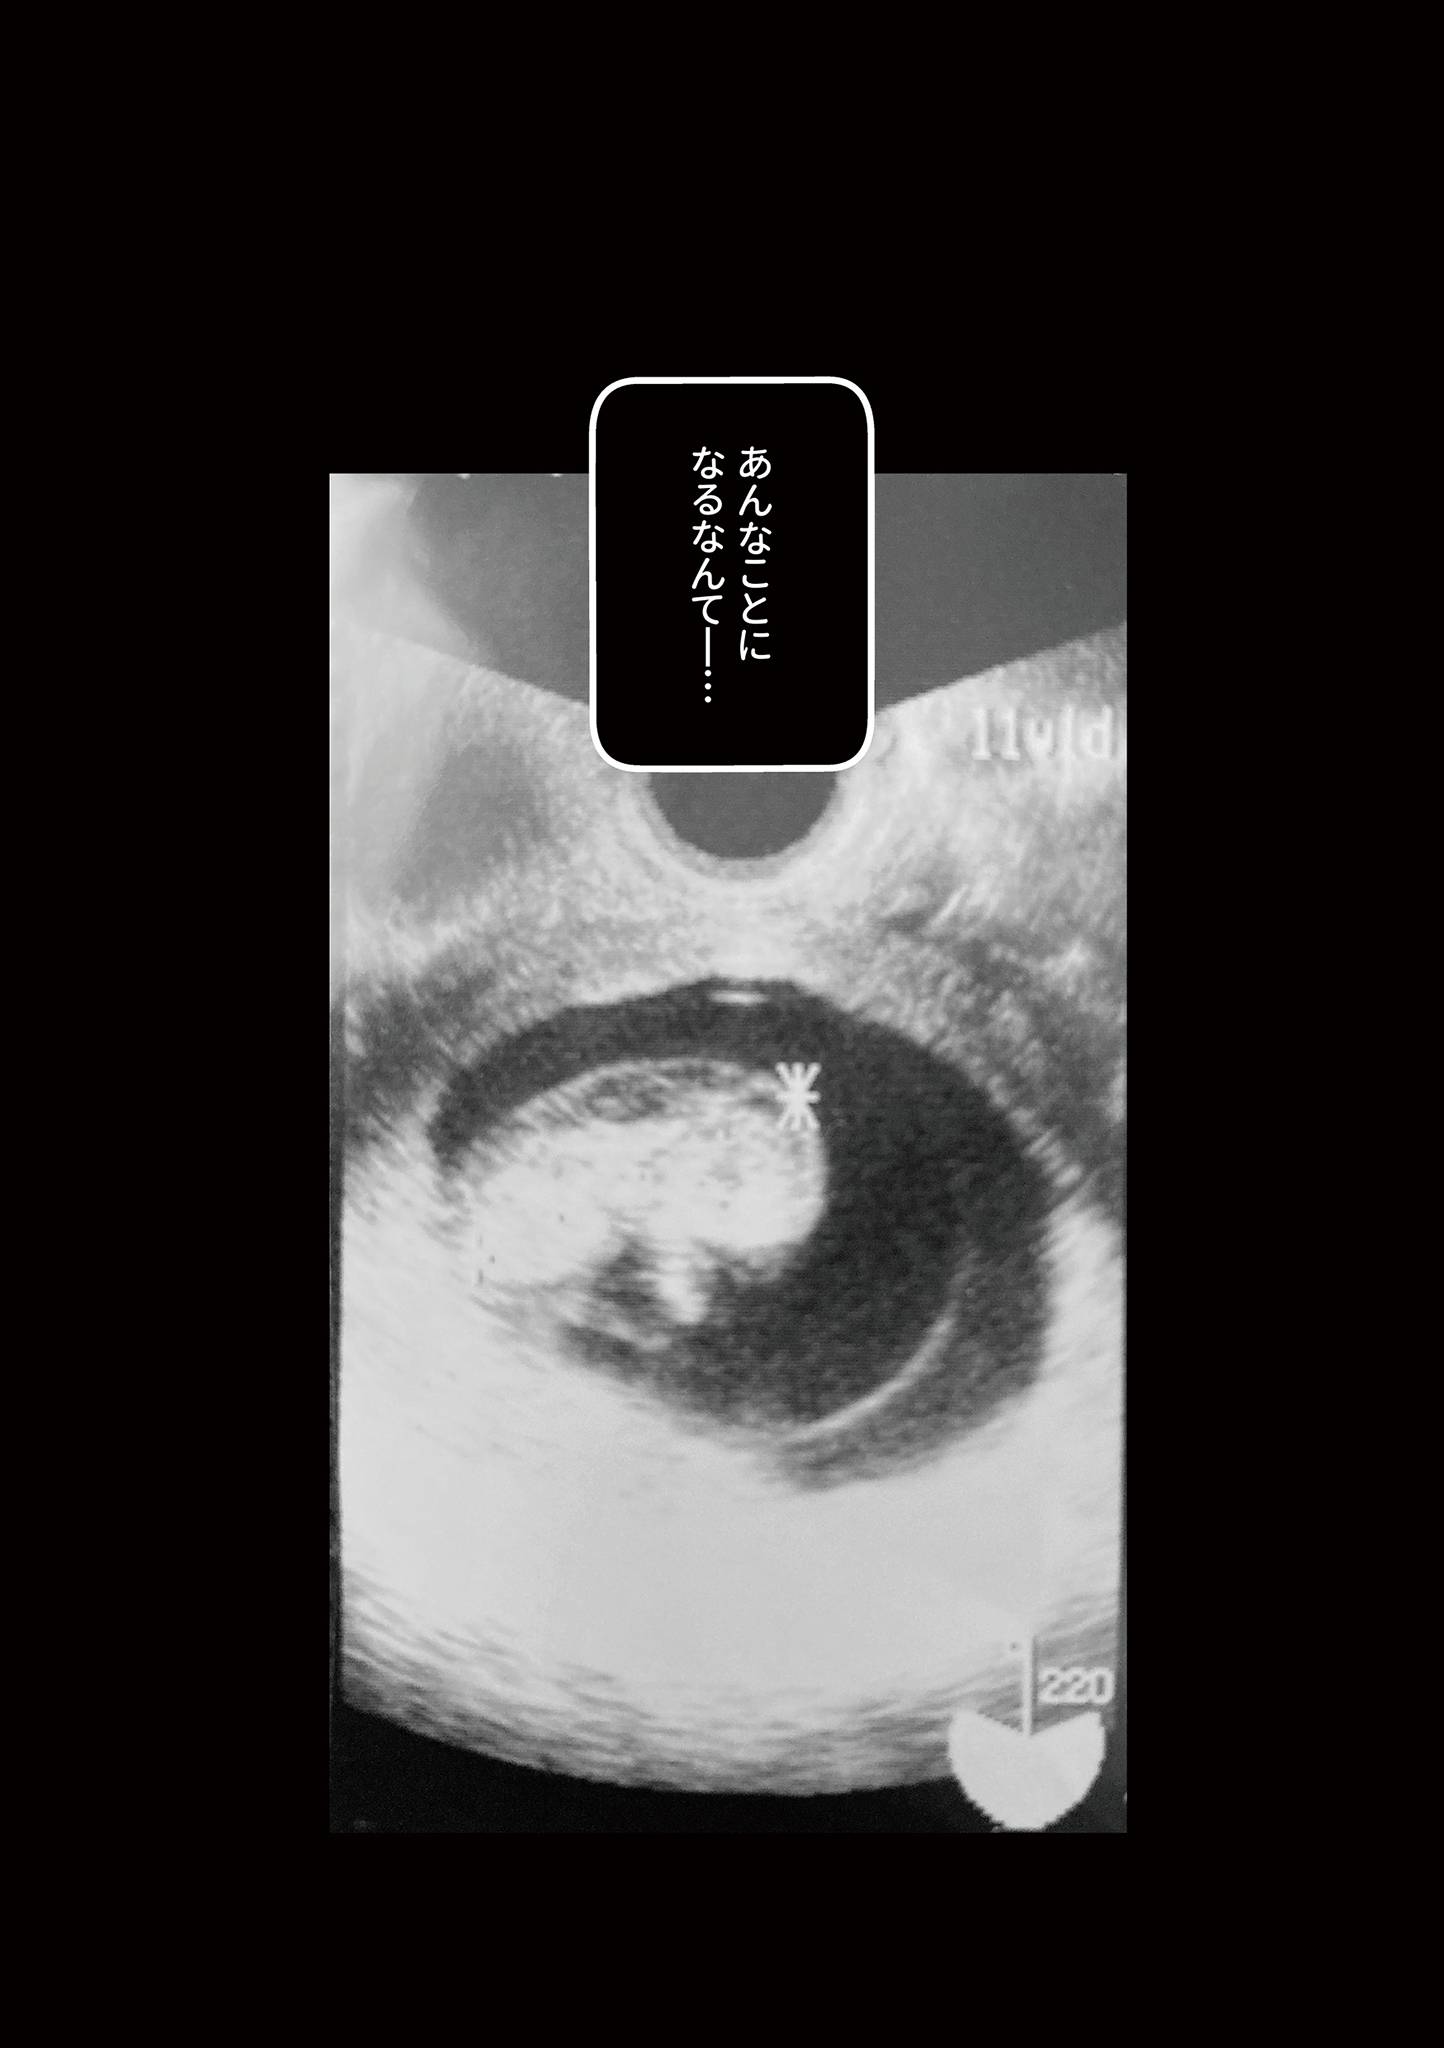

【漫画】「2人目はまだ?」待ちに待った2人目の赤ちゃんは18トリソミーという染色体異常だった

桜木きぬさんは、夫と5歳の長男と3人暮らし。「2人目は?」と聞かれることもありますが、なかなか授かることができませんでした。ある日、妊娠検査薬には「陽性」の判定が。念願の妊娠でしたが、赤ちゃんは18トリソミーという染色体異常で、後に「死産」という選択をすることになります。※本記事は『わたしが選んだ死産の話』(KADOKAWA)より編集・抜粋しました。